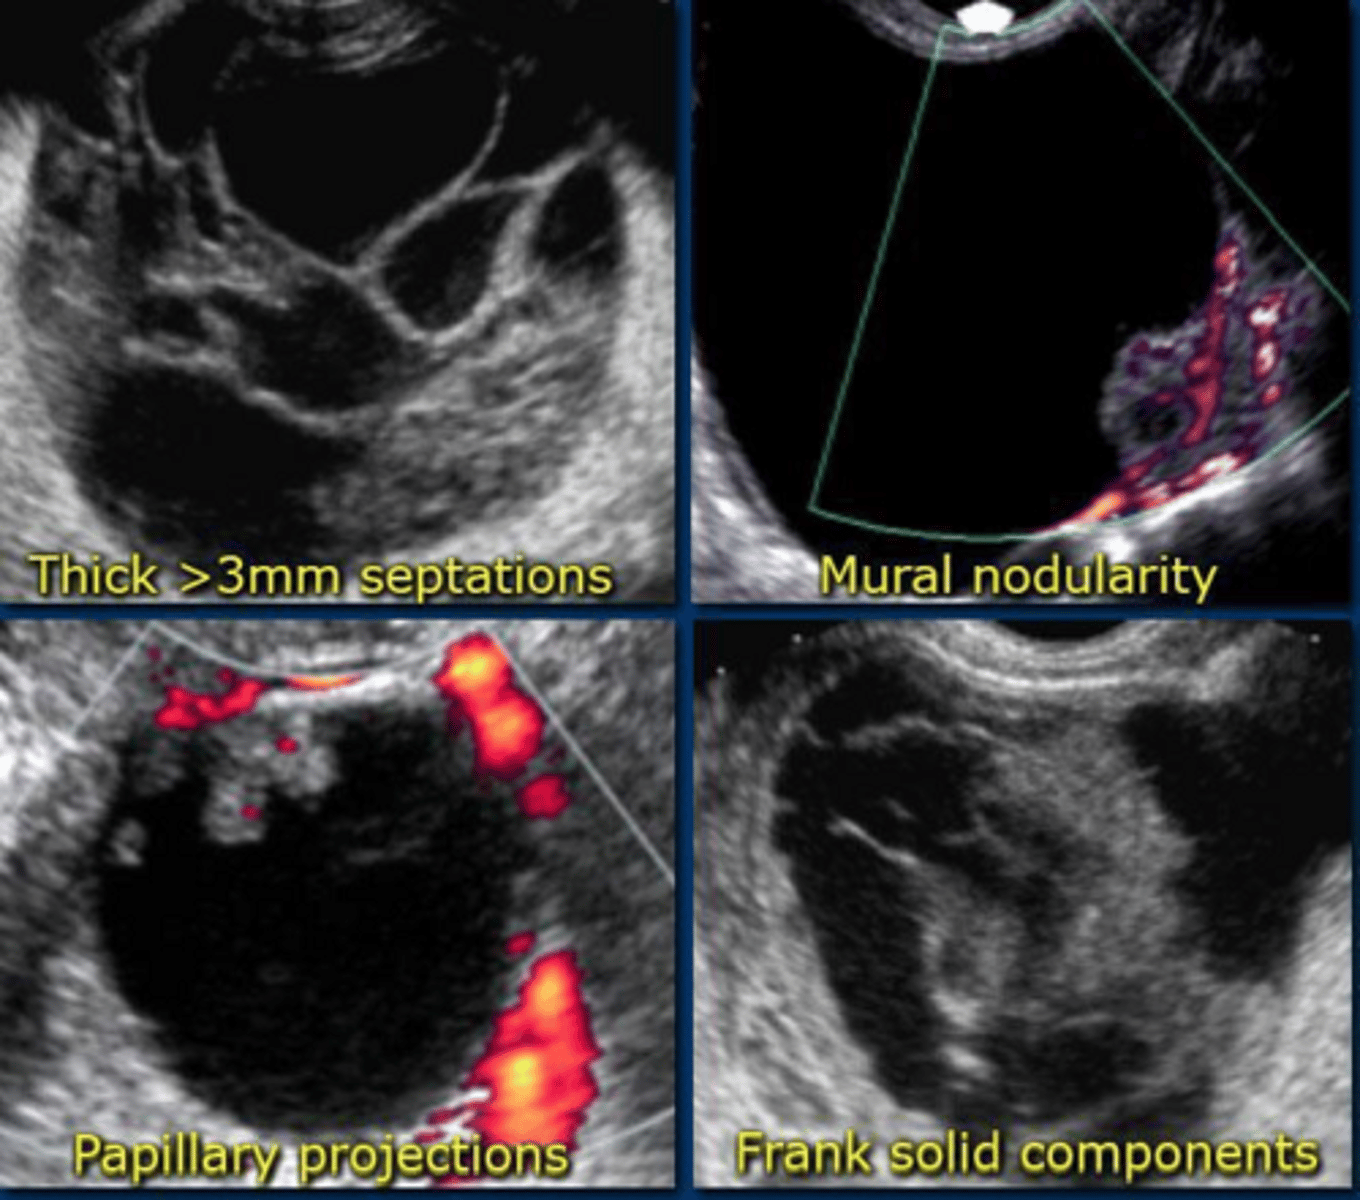

What are the ultrasound characteristics of a malignant adnexal mass?

Solid components, thick septations, irregular borders, and internal vascularity on Doppler.